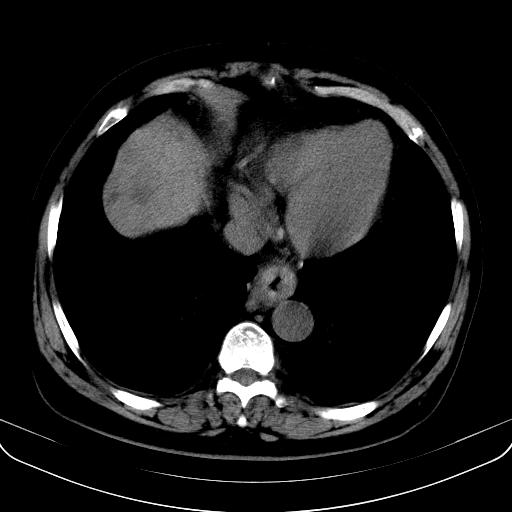

以下是引用jia119在2008-3-5 13:31:00的发言:[br]肝内多发片状低密度影,密度不均,我还是考虑肝ca可能,另肝内小囊肿,胆囊增大。

以下是引用形影不离在2008-3-5 12:18:00的发言:[br]肝硬化伴门脉高压征,肝内占位待排,增强再说.

以下是引用随光逐影在2008-3-5 21:11:00的发言:[br]肝硬化伴门脉高压(食管下段静脉曲张),肝癌不排除。建议:行ct增强扫描检查。

以下是引用同在2008-3-5 13:56:00的发言:[br]考虑肝癌可能性大,胆囊增大.